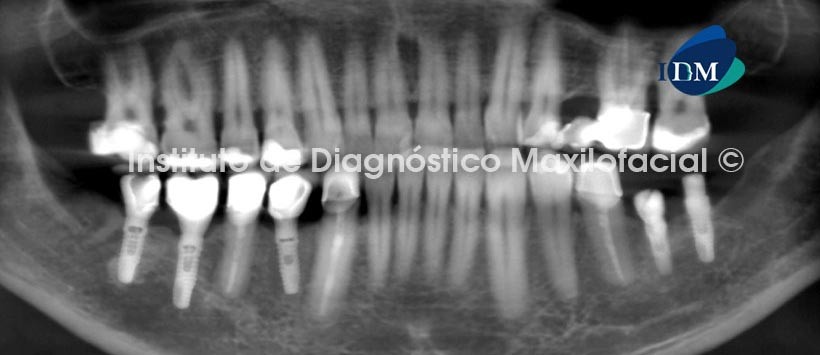

Se procedió a la evaluación con tomografía computarizada de Haz Cónico.

A la evaluación del cuadrante III en mención se pudo observar a nivel de la pieza 3.6 un implante en falsa vía con compromiso de la tabla ósea lingual, sin afectación del conducto dentario, se hizo la evaluación de todos los implantes dentales encontrándose en aparente óseo integración sin afectación de corticales y conservación del conducto dentario. (Fig. 2,3,4,5,6)